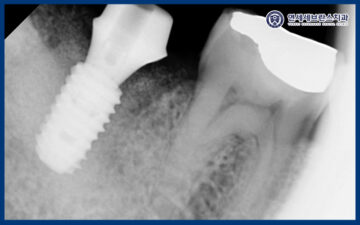

24.08.14

먼저 발치를 진행하였으며

치조골 소실로 인해 뼈가 부족하여

뼈이식을 동반하여 곡반정동임플란트

식립을 하였습니다.

25.01.07

임플란트는 초기 고정력이

무엇보다 중요한 치료이기 때문에,

식립 후 한 달 뒤 내원하셨을 때

다시 촬영을 통해

상태를 확인하였습니다.

촬영 결과를 바탕으로

고정이 잘 이루어지고 있는지,

주변 치조골과 잇몸의 회복 상태를

세심하게 평가하였습니다.